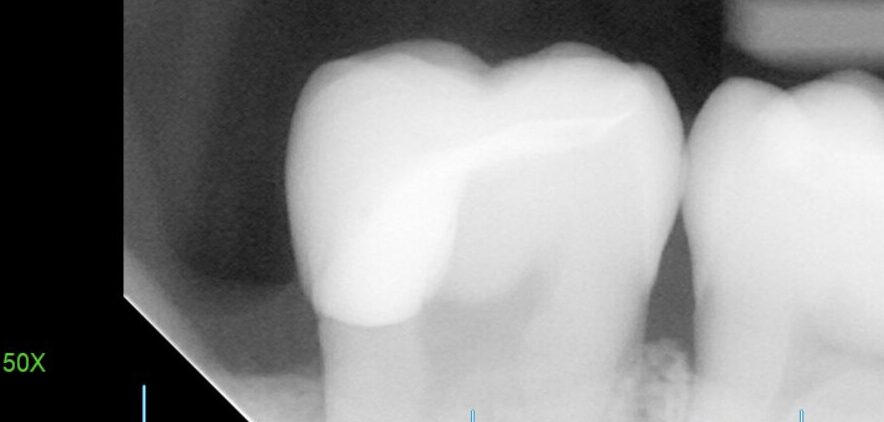

患者様は親知らずが痛み来院されました。レントゲン検査で調べた所、一つ前の歯(大臼歯)に大きな虫歯が認められたため、治療の必要性とメリットデメリットをお話しし、ご本人様は再発率の低い治療をご希望されました。

精密に治療するためにはまずはVPT(歯髄温存療法)を行い神経を温存し、根管治療を回避、その後親知らずを抜歯して間を空けずにオーバーレイ(テーブルトップベニヤ)を作成していく必要があります。患者様と綿密にスケジュールを練り、施術に挑みました。